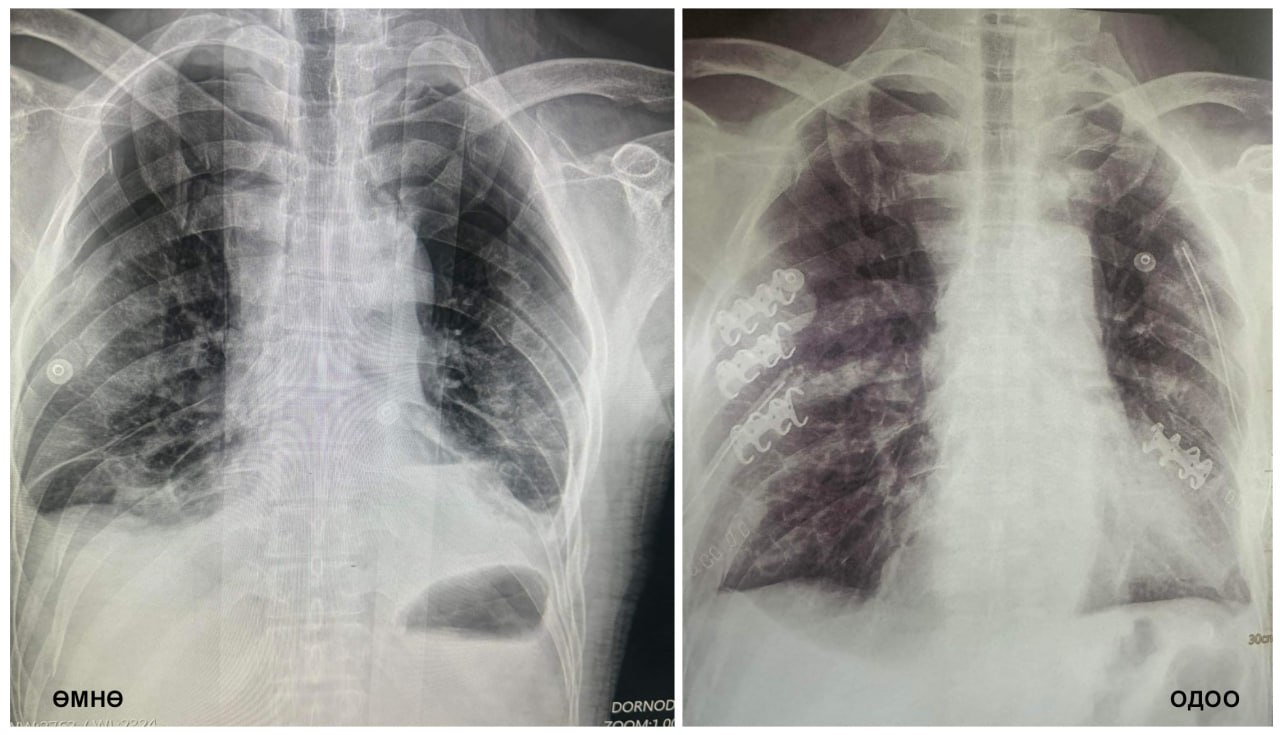

Гэмтэл согог судлалын үндэсний төвийн Хавсарсан гэмтлийн мэс заслын тасгийн эрхлэгч П.Баярсайхан, Мэс засал, мэдээгүйжүүлэгийн нэгдсэн тасгийн сувилагч Б.Бямбацэцэг, жолооч Д.Энхжаргал нарын алсын дуудлагын баг өнгөрөгч амралтын өдрүүдэд Дорнод аймагт ажиллаж, олон хавирганы тогтворгүй хугарал болон цээжний хөндийн битүү гэмтэл хавсарсан хүнд өвчтөнд мэс заслын яаралтай тусламж үзүүллээ.

Тодруулбал, ГССҮТ-ийн алсын дуудлагын баг бүрэлдэхүүн аймгийн Эрүүл мэндийн төвийн Гэмтлийн тасгийн эрхлэгч Т.Энхтулга, их эмч Э.Эрдэнэбаяр, Т.Лхагважав, Б.Анхбаяр, мэдээгүйжүүлэгийн эмч Б.Саруултөгс, мэдээгүйжүүлэгийн сувилагч Г.Отгонтуяа, мэс заслын сувилагч Б.Мягмарнаран, туслах сувилагч Б.Баасанцэрэн нартай хамтран мэс засал эмчилгээг амжилттай хийсэн байна.

Өвчтөний биеийн байдал тогтворжиж, Эрчимт эмчилгээний тасагт мэс заслын дараах эмчилгээ хийлгэж буй бөгөөд алсын дуудлагын баг нийслэл рүү буцах замдаа авто осолд орсон иргэдэд яаралтай тусламж үзүүлж, хунгар цасанд суусан 2 адууг цаснаас гаргаж ижил сүрэгтэй нь нийлүүлжээ. ГССҮТ-ийн Хавсарсан гэмтлийн мэс заслын тасгийн эмч, мэргэжилтнүүд цээжний хөндийн битүү гэмтэл, олон хавирганы тогтворгүй хугарлыг бэхлэх мэс засал эмчилгээг эх орондоо нутагшуулан, эмнэлгийн тусламж үйлчилгээнд өдгөө 6 дахь жилдээ хэрэгжүүлэн ажиллаж байгаа билээ.